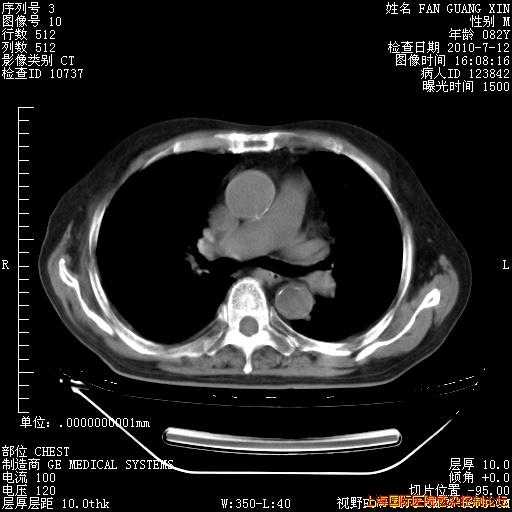

今天复查CT

今天CT

整整相隔30天的肺部CT好像有所好转啊。甲强龙减量第3天,需要观察体温。

海管,自昨日你和我通完话后,不知您岳父消化道症状有无缓解?体温怎样?阅读7.12日胸部ct,个人认为目前激素治疗是有效的,甲强龙减量是适宜的。因在抗痨治疗,需密切观察肝功、肾功能和血常规。不过,老年、长期住院和大量使用激素,很担心菌群失调发生